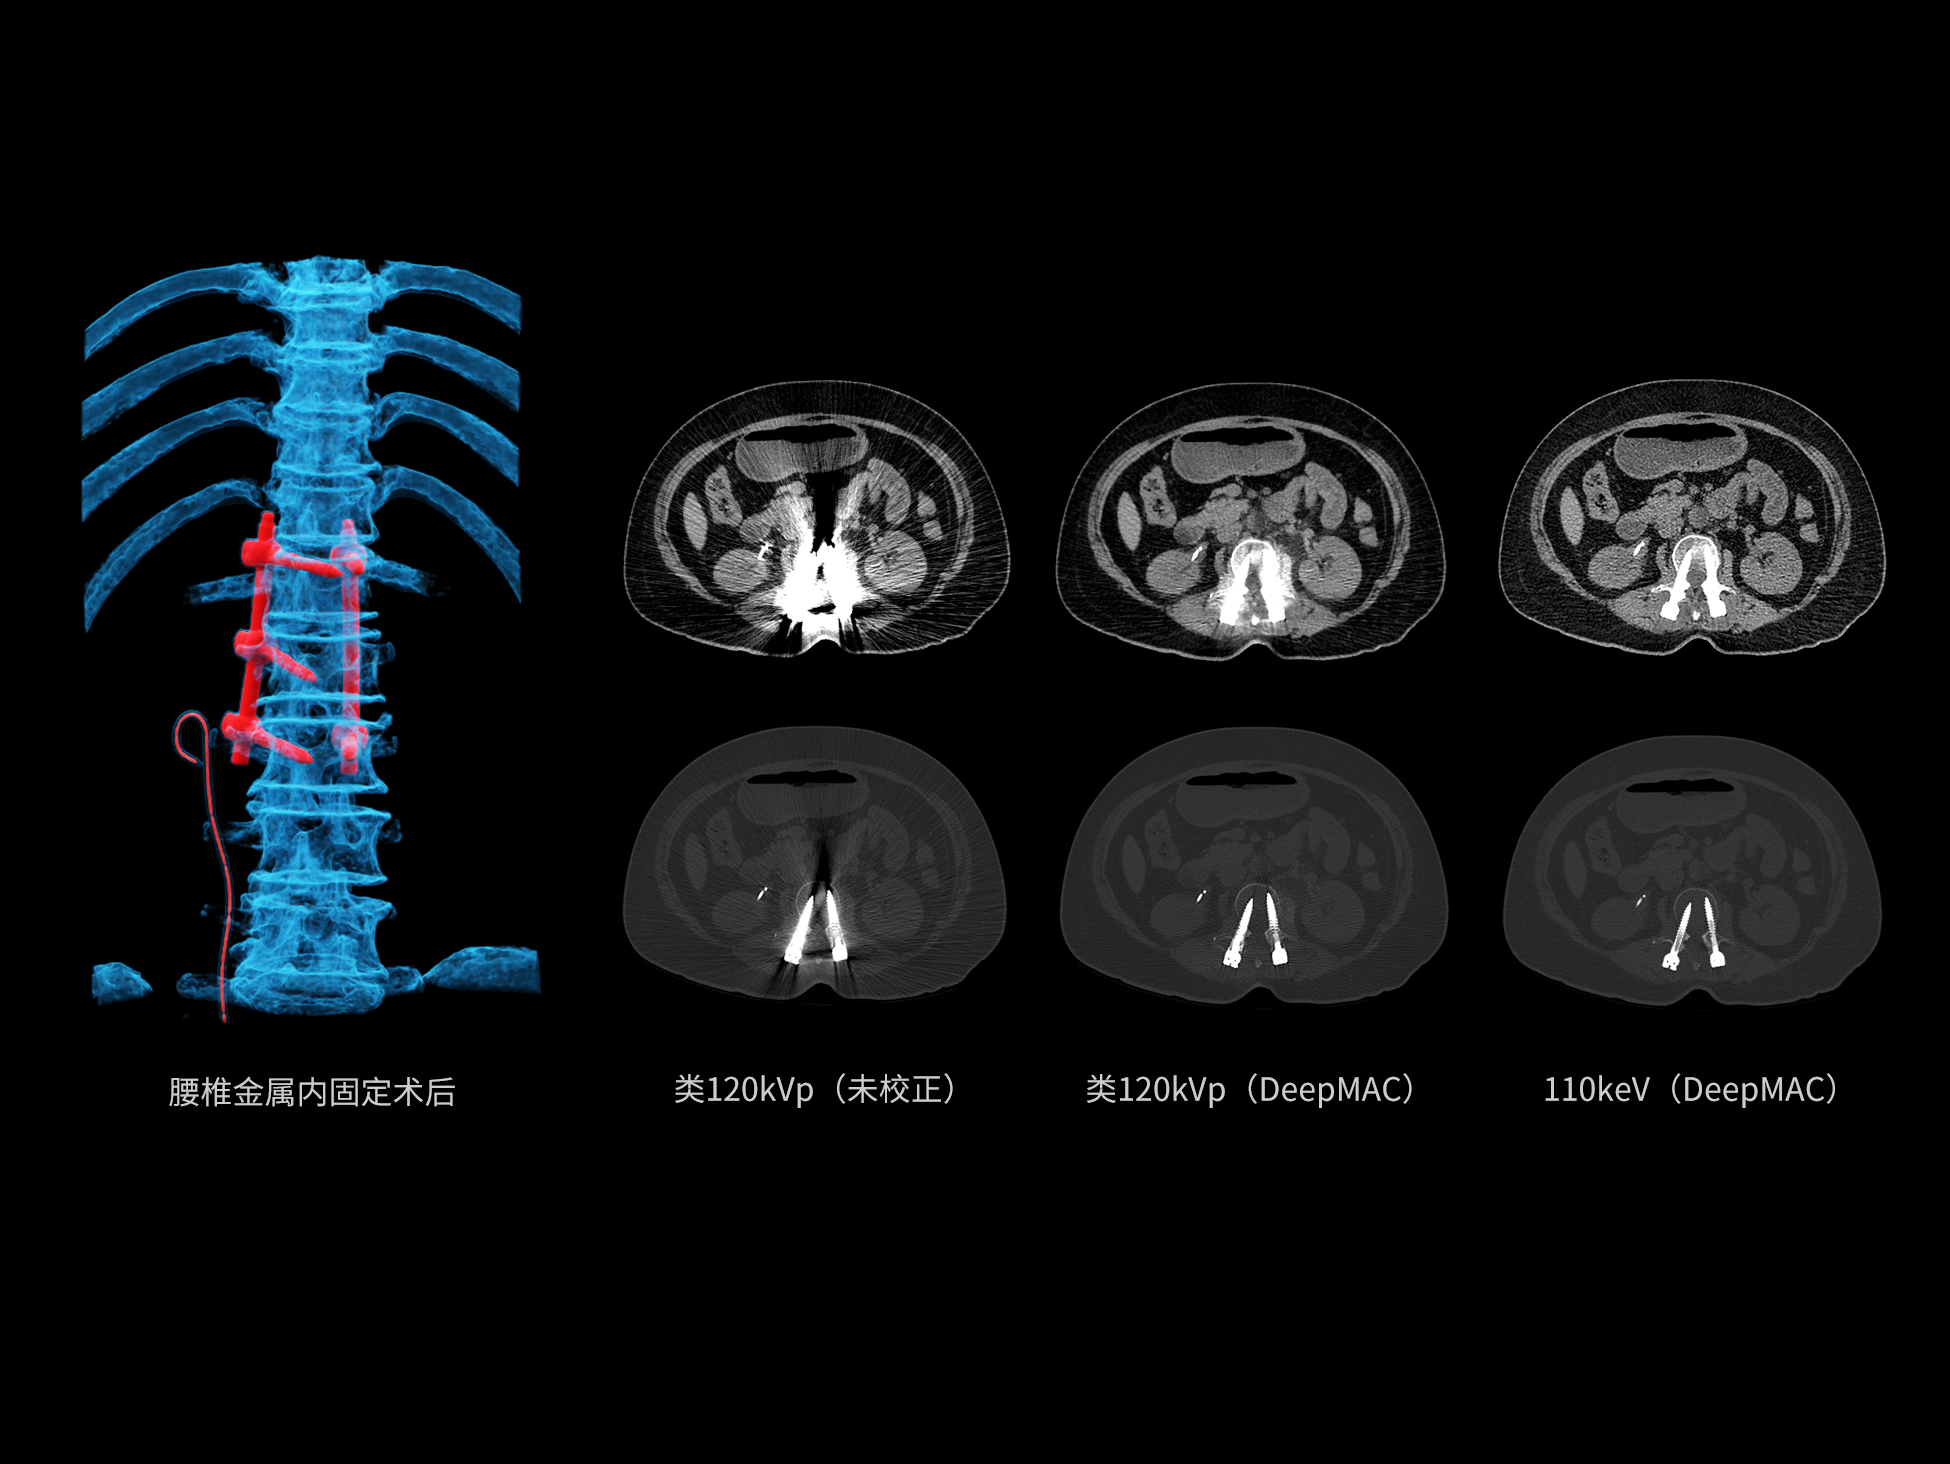

去金属伪影,影像更纯净

uCT SiriuX® 提供系统化金属伪影抑制解决方案。能谱扫描结合 PureBeam 纯光滤能技术,从源头有效减少硬化伪影;DeepMAC深度学习金属伪影校正算法针对射线饥饿、散射等多种成因进行优化重建,从物理与算法双层面显著提升金属植入区域的图像质量与可诊断性。

高能级虚拟单能成像

双宽能谱成像提供高能级虚拟单能图像,结合硬化伪影校正技术,有效提升金属与组织对比度,源头抑制金属物质类硬化伪影。

PureBeam纯光滤能技术

球管端采用锡材质滤过,有效滤过低能光子,提升能谱扫描的高低能分离度,减少能量重叠。

DeepMAC深度学习金属伪影校正算法

基于深度学习网络模型,应对髋关节置换体、脊柱内固定器、四肢骨科植入物、牙科修复体以及血管介入弹簧圈等各类金属植入物伪影,还原清晰解剖结构。